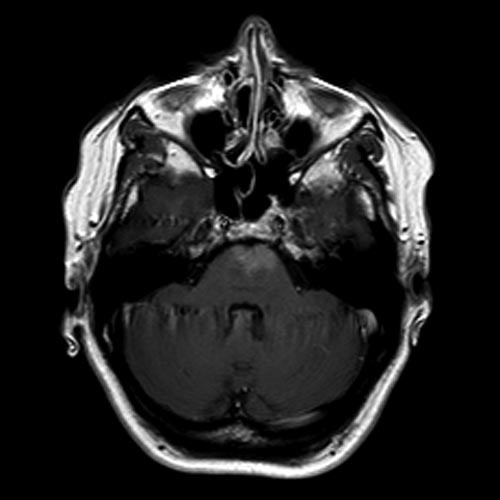

Note the multiple sites of oedema and haemorrhage, involving the brain stem and corpus callosum as well as subcortical white matter and left cerebral peduncle. High FLAIR signal is also seen in the dorsal midbrain. EVD insitu.

Case Discussion

Diffuse axonal injury can be subtle on CT but have devastating consequences for the patient. This is a case of grade III injury (involvement of brainstem) and carries a poor prognosis.

Diffuse axonal injury (DAI), also known as traumatic axonal injury (TAI), is a severe form of traumatic brain injury due to shearing forces. It is a potentially difficult diagnosis to make on imaging alone, especially on CT as the finding can be subtle, however, it has the potential to result in severe neurological impairment.

The diagnosis is best made on MRI where it is characterised by several small regions of susceptibility artifact at the grey-white matter junction, in the corpus callosum, and in more severe cases in the brainstem, surrounded by FLAIR hyperintensity.

Diffuse axonal injury is characterised by multiple focal lesions with a characteristic distribution: typically located at the grey-white matter junction, in the corpus callosum and in more severe cases in the brainstem (see: grading of diffuse axonal injury).

The appearance depends on whether or not the lesions are overtly haemorrhagic. Haemorrhagic lesions will be hyperdense and range in size from a few millimetres to a few centimetres in diameter. Non-haemorrhagic lesions are hypodense. They typically become more evident over the first few days as oedema develops around them. They may be associated with significant and disproportionate cerebral swelling.

MRI is the modality of choice for assessing suspected diffuse axonal injury even in patients with entirely normal CT of the brain 5,6. MRI, especially SWI or GRE sequences, exquisitely sensitive to paramagnetic blood products may demonstrate small regions of susceptibility artefact at the grey-white matter junction, in the corpus callosum or the brain stem. Some lesions may be entirely non-haemorrhagic (even using high field strength SWI sequences). These will, however, be visible as regions of high FLAIR signal.